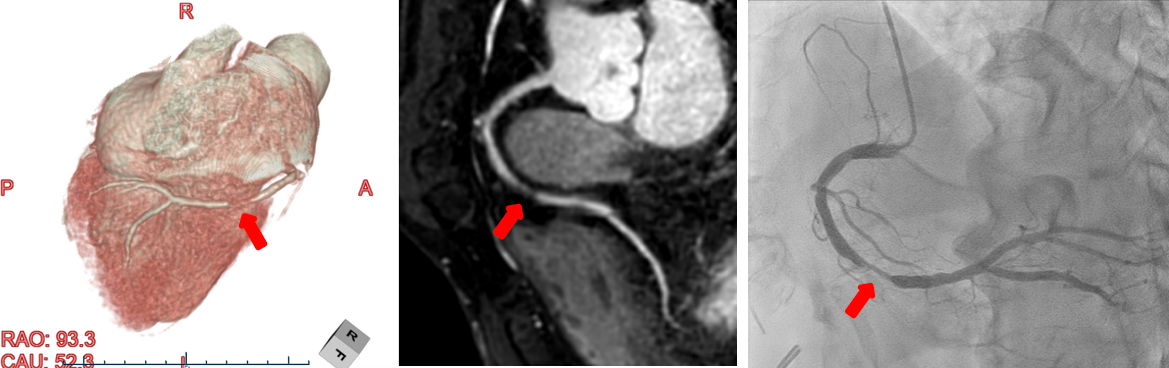

非造影のMRI冠動脈画像(左,中央)にて,右冠動脈に狭窄病変が疑われ,カテーテルによる冠動脈造影検査(右)でも,同じ部位に狭窄病変が認められました.